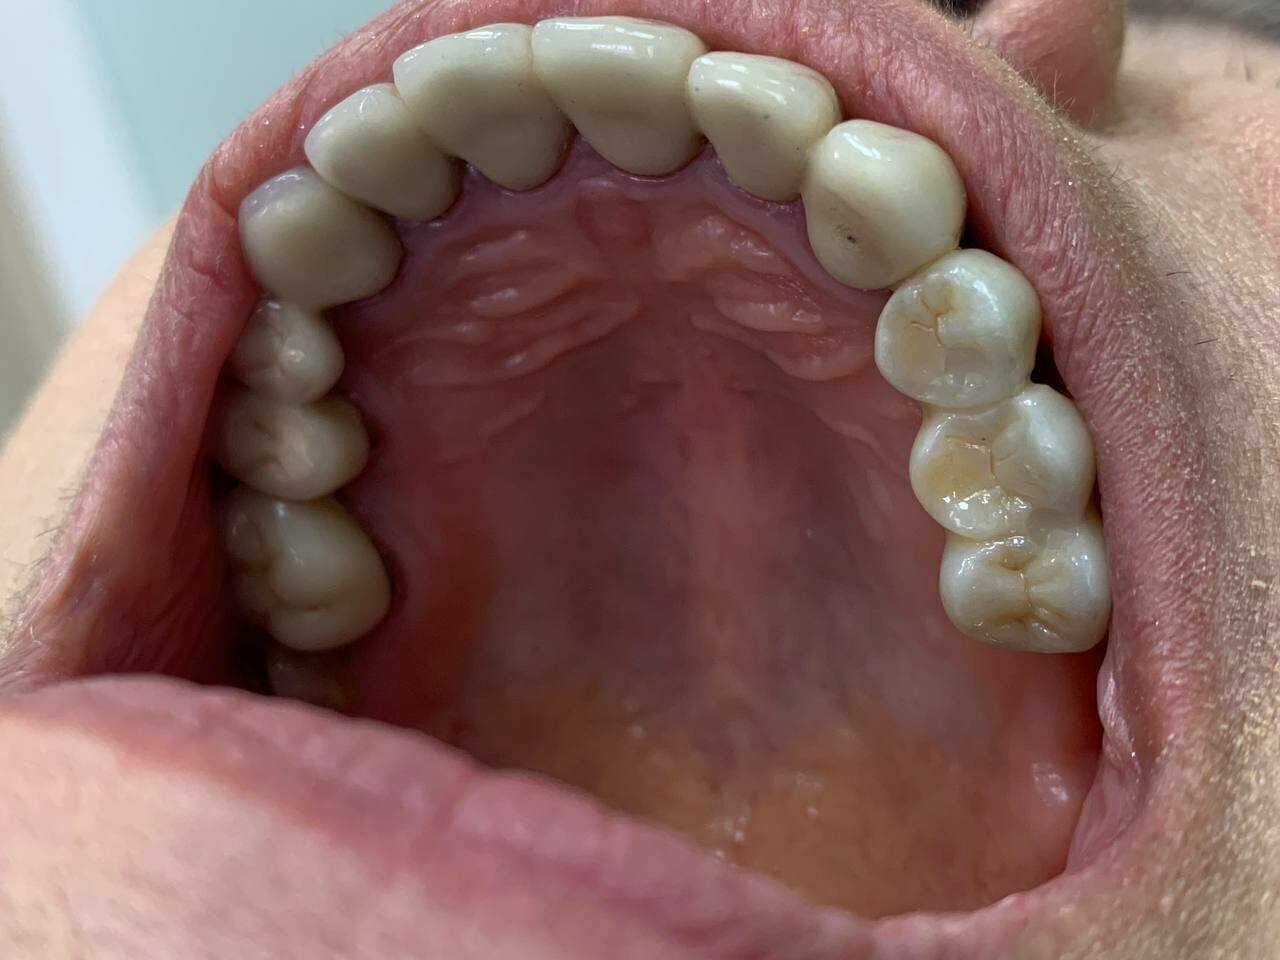

«Сити Дент» охватывает все основные направления стоматологии, включая общую стоматологию, ортодонтию, хирургию, эстетическую и детскую стоматологию. В клинике применяются современные технологии, такие как цифровая стоматология CAD/CAM, лечение под микроскопом, компьютерная томография и рентгенография. Среди дополнительных услуг — имплантология, костная пластика, гнатология, элайнеры, виниры, люминиры, отбеливание, протезирование и челюстно-лицевая хирургия.

Лоцманов Алексей Владимирович я считаю опытный и очень хороший врач имплантолог! Отношение к клиентам у него подчеркнуто вежливое! Оборудование современное. Юмор в ходе операции- его сильная сторона. Никаких проблем в ходе имплантации мне 6 имплантов 29.05.2024 г., не возникло. Последствия операции только положительные! Моё лечение продолжается, но самое страшное уже позади. Всем знакомым буду рекомендовать эту клинику.